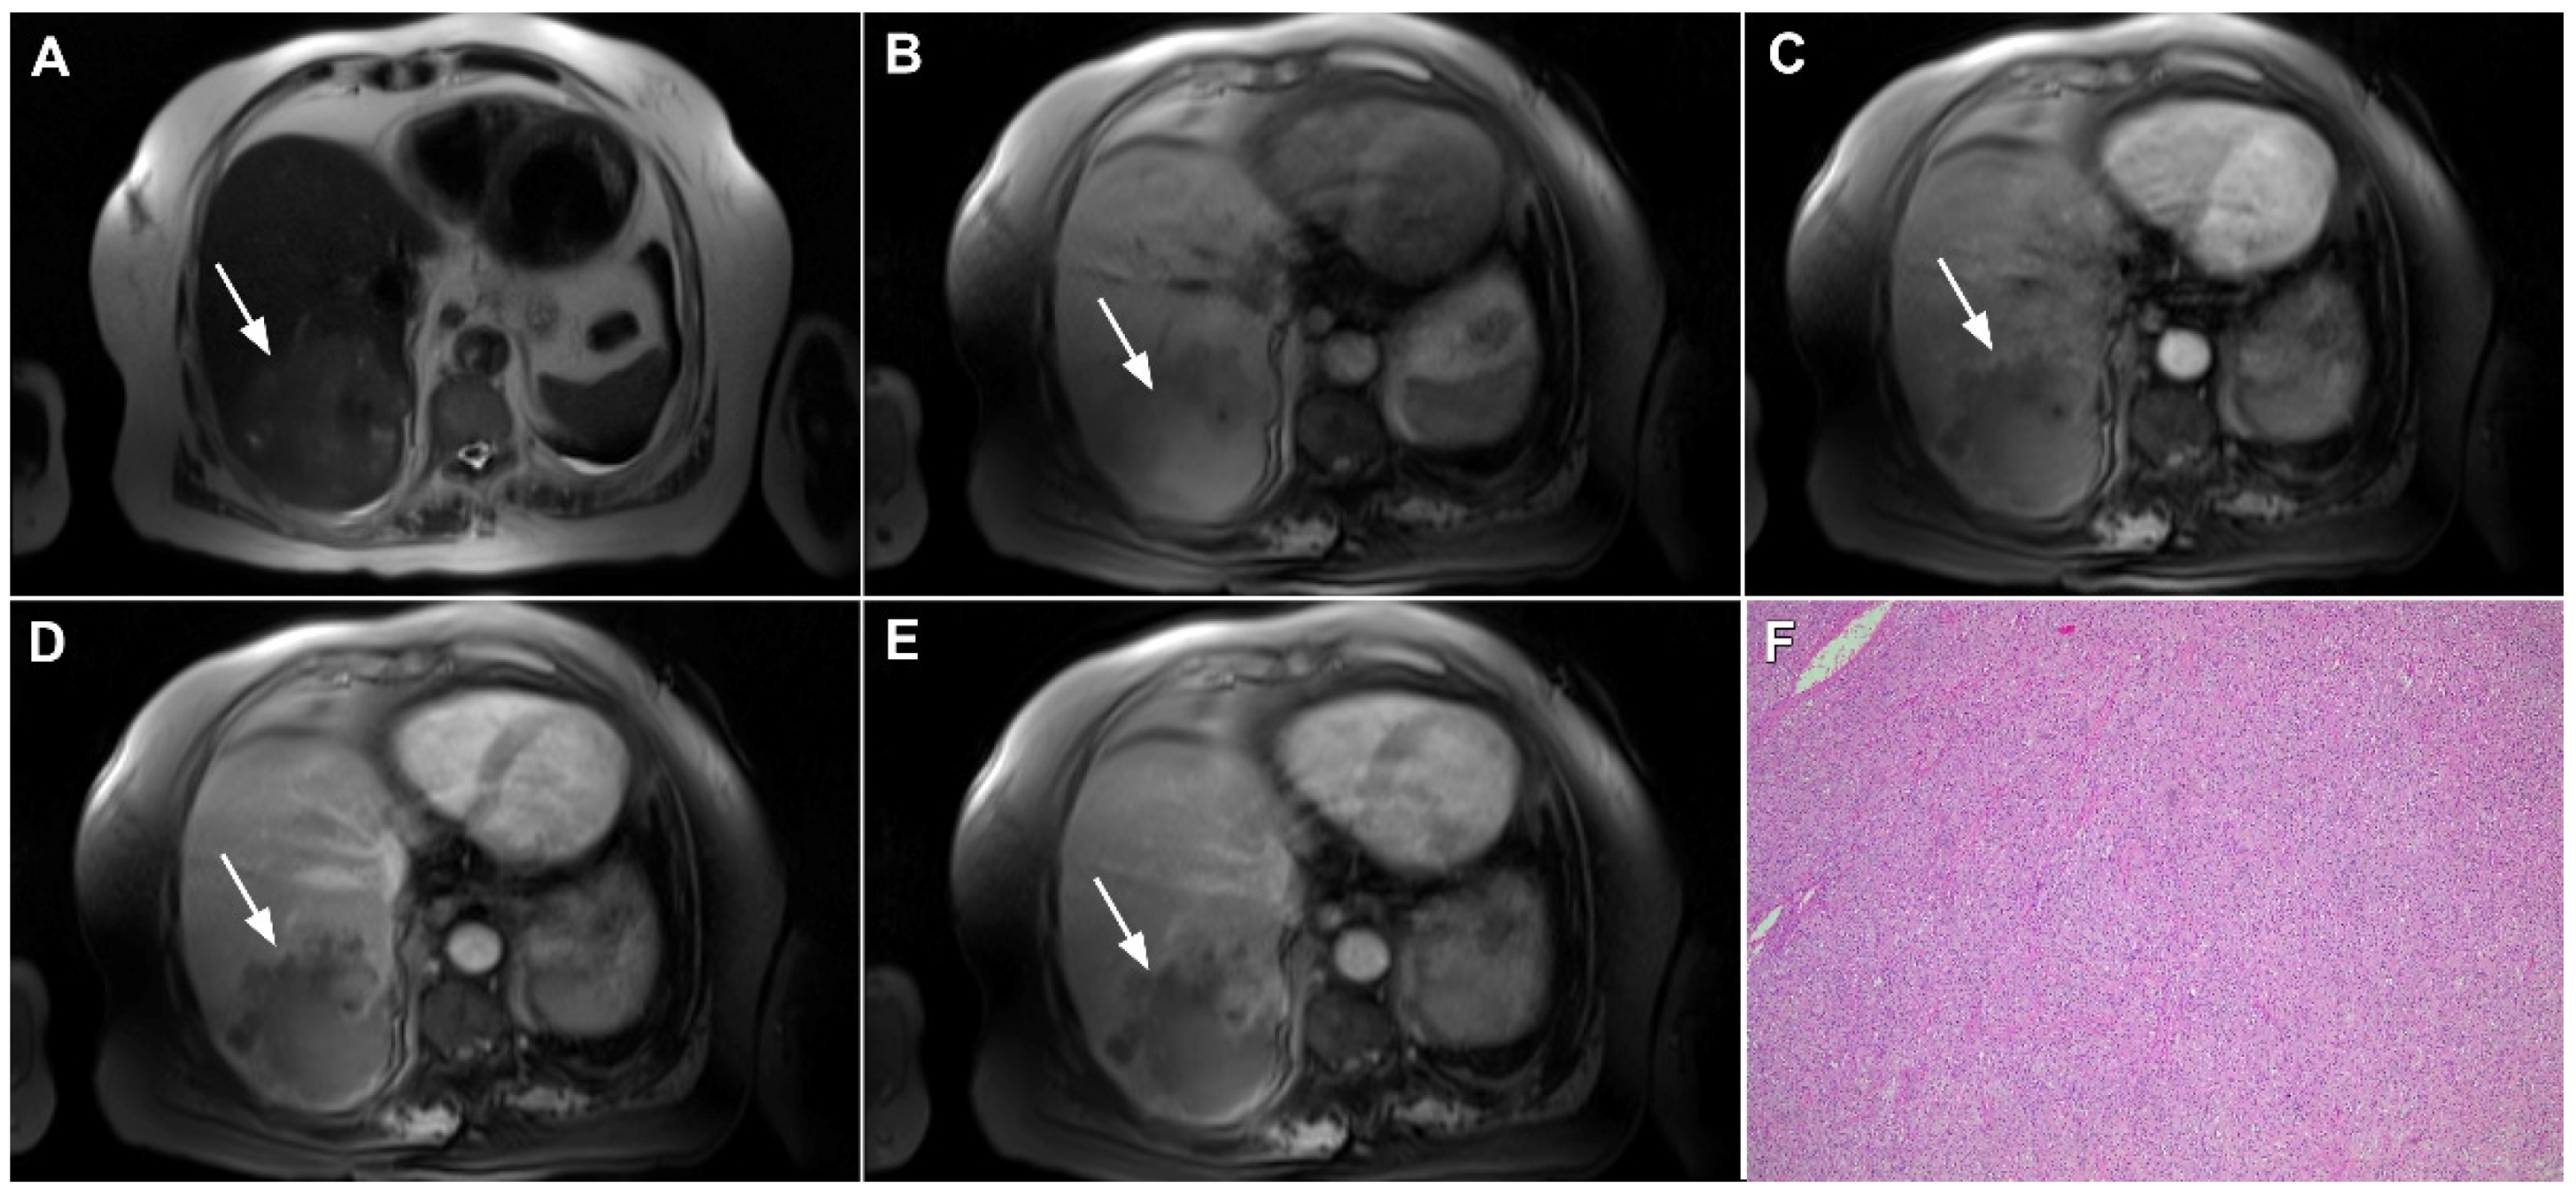

3.2.5. Primary Hepatic Lymphoma

- Lei, K.I. Primary non-Hodgkin’s lymphoma of the liver. Leuk. Lymphoma 1998, 29, 293–299. [Google Scholar] [CrossRef]

- Peng, Y.; Qing, A.C.; Cai, J.; Yue, C.; French, S.W.; Qing, X. Lymphoma of the liver: Clinicopathological features of 19 patients. Exp. Mol. Pathol. 2016, 100, 276–280. [Google Scholar] [CrossRef]

- Appelbaum, L.; Lederman, R.; Agid, R.; Libson, E. Hepatic lymphoma: An imaging approach with emphasis on image-guided needle biopsy. Isr. Med. Assoc. J. 2005, 7, 19–22. [Google Scholar] [PubMed]

- Colagrande, S.; Calistri, L.; Grazzini, G.; Nardi, C.; Busoni, S.; Morana, G.; Grazioli, L. MRI features of primary hepatic lymphoma. Abdom. Radiol. 2018, 43, 2277–2287. [Google Scholar] [CrossRef]

- Rajesh, S.; Bansal, K.; Sureka, B.; Patidar, Y.; Bihari, C.; Arora, A. The imaging conundrum of hepatic lymphoma revisited. Insights Imaging 2015, 6, 679–692. [Google Scholar] [CrossRef]

- Ippolito, D.; Porta, M.; Maino, C.; Pecorelli, A.; Ragusi, M.; Giandola, T.; Querques, G.; Talei Franzesi, C.; Sironi, S. Diagnostic approach in hepatic lymphoma: Radiological imaging findings and literature review. J. Cancer Res. Clin. Oncol. 2020, 146, 1545–1558. [Google Scholar] [CrossRef] [PubMed]